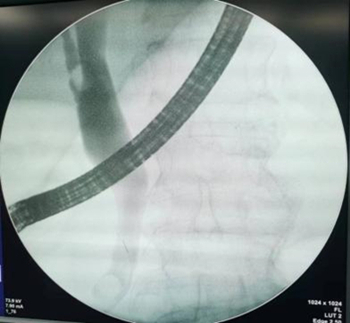

在迅速完善术前准备后,消化内科主任杨晓军主任和副主任王征球为患者实施了内镜下逆行胰胆管造影+胆道塑料支架置入+鼻胆管引流术。术中,杨晓军主任成功地将导丝插入了胆总管,完成切开、引流、造影、放置支架等一项项操作。考虑到患者血压不稳定,为了缩短手术时间,保障患者生命安全,杨晓军主任迅速放置了胆道支架及鼻胆管后退镜。手术全程仅用时20分钟,术后患者病情平稳,恢复良好。